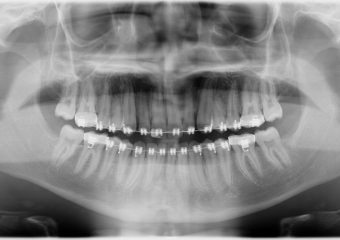

Rx Panoramico - Tracionamento finalizado - Clínica Cliniface

Rx Panoramico - Tracionamento finalizado